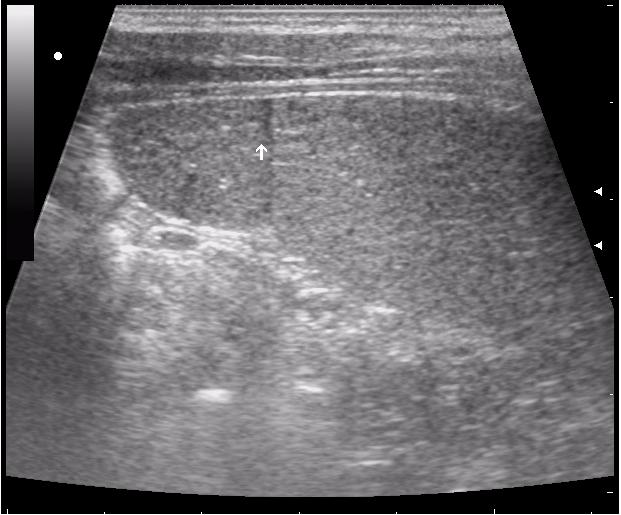

>желтой стрелкой - это левый надпочечник?

Похоже.

Он обычно располагается больше кнутри от верхнего полюса почки и может досигать ее ворот.

Надежнее визуализировать ЛН из позиции, которую я показывал в известной Вам теме.